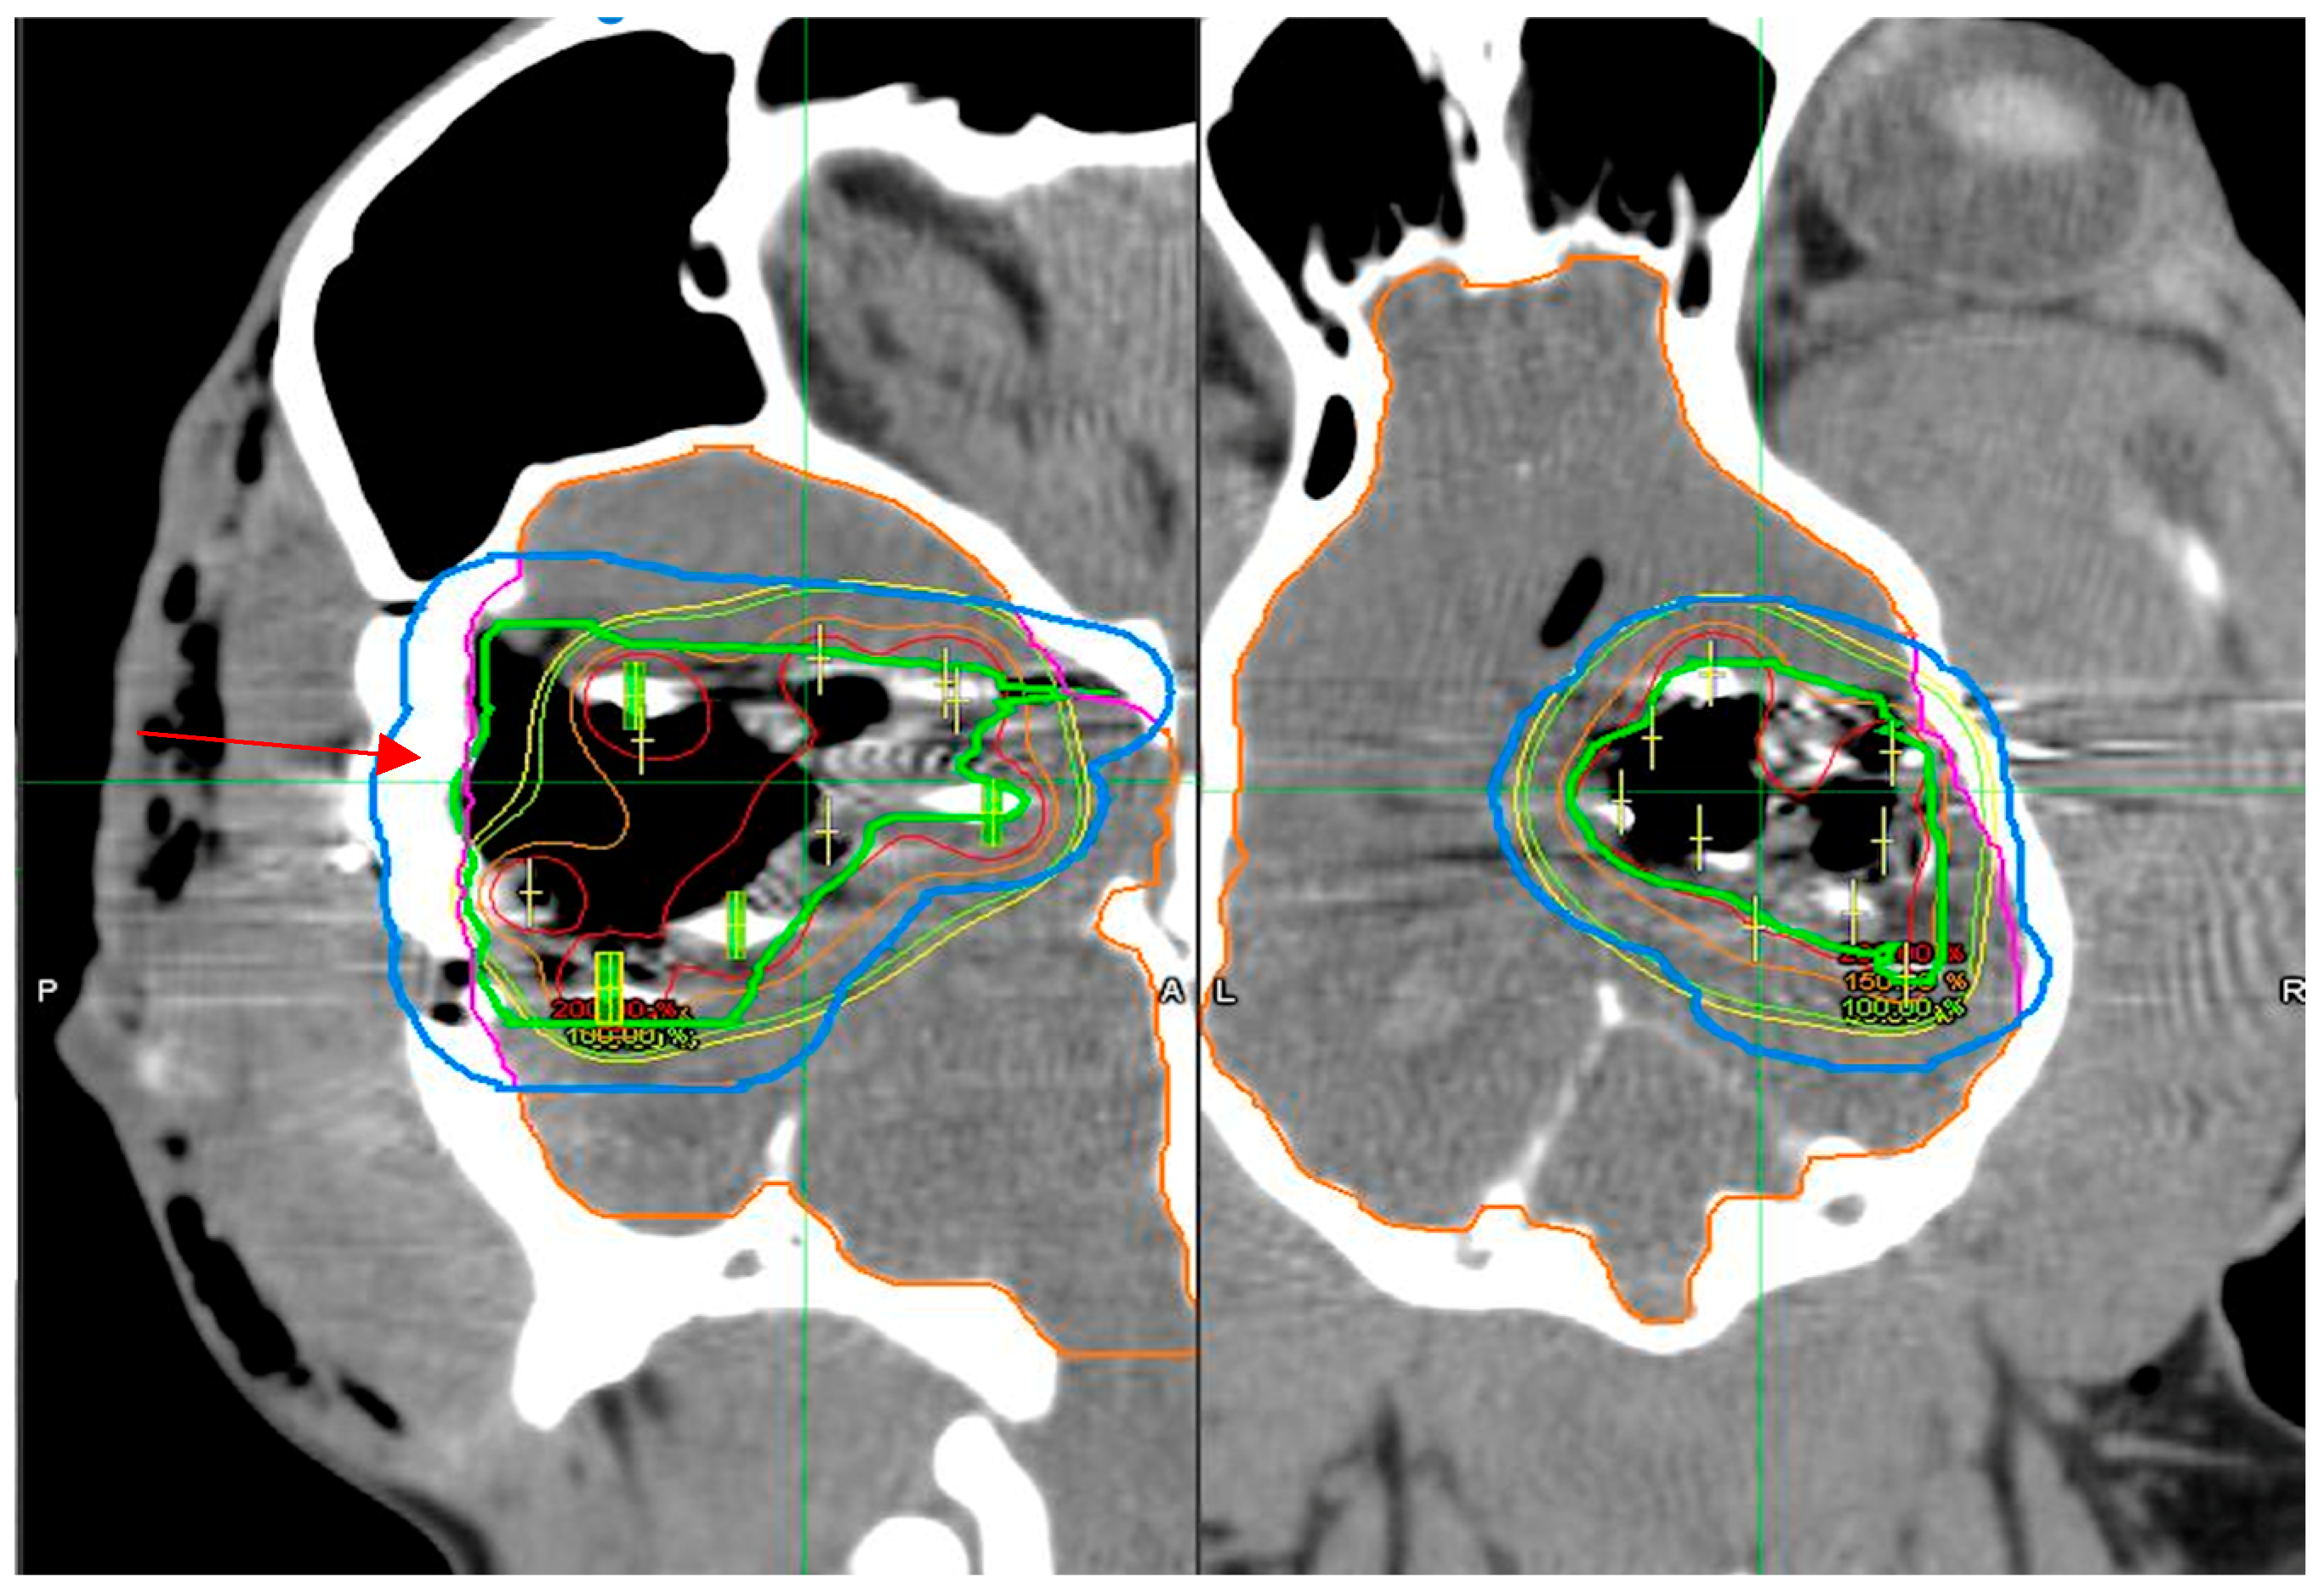

3.3. Dosimetry Verification